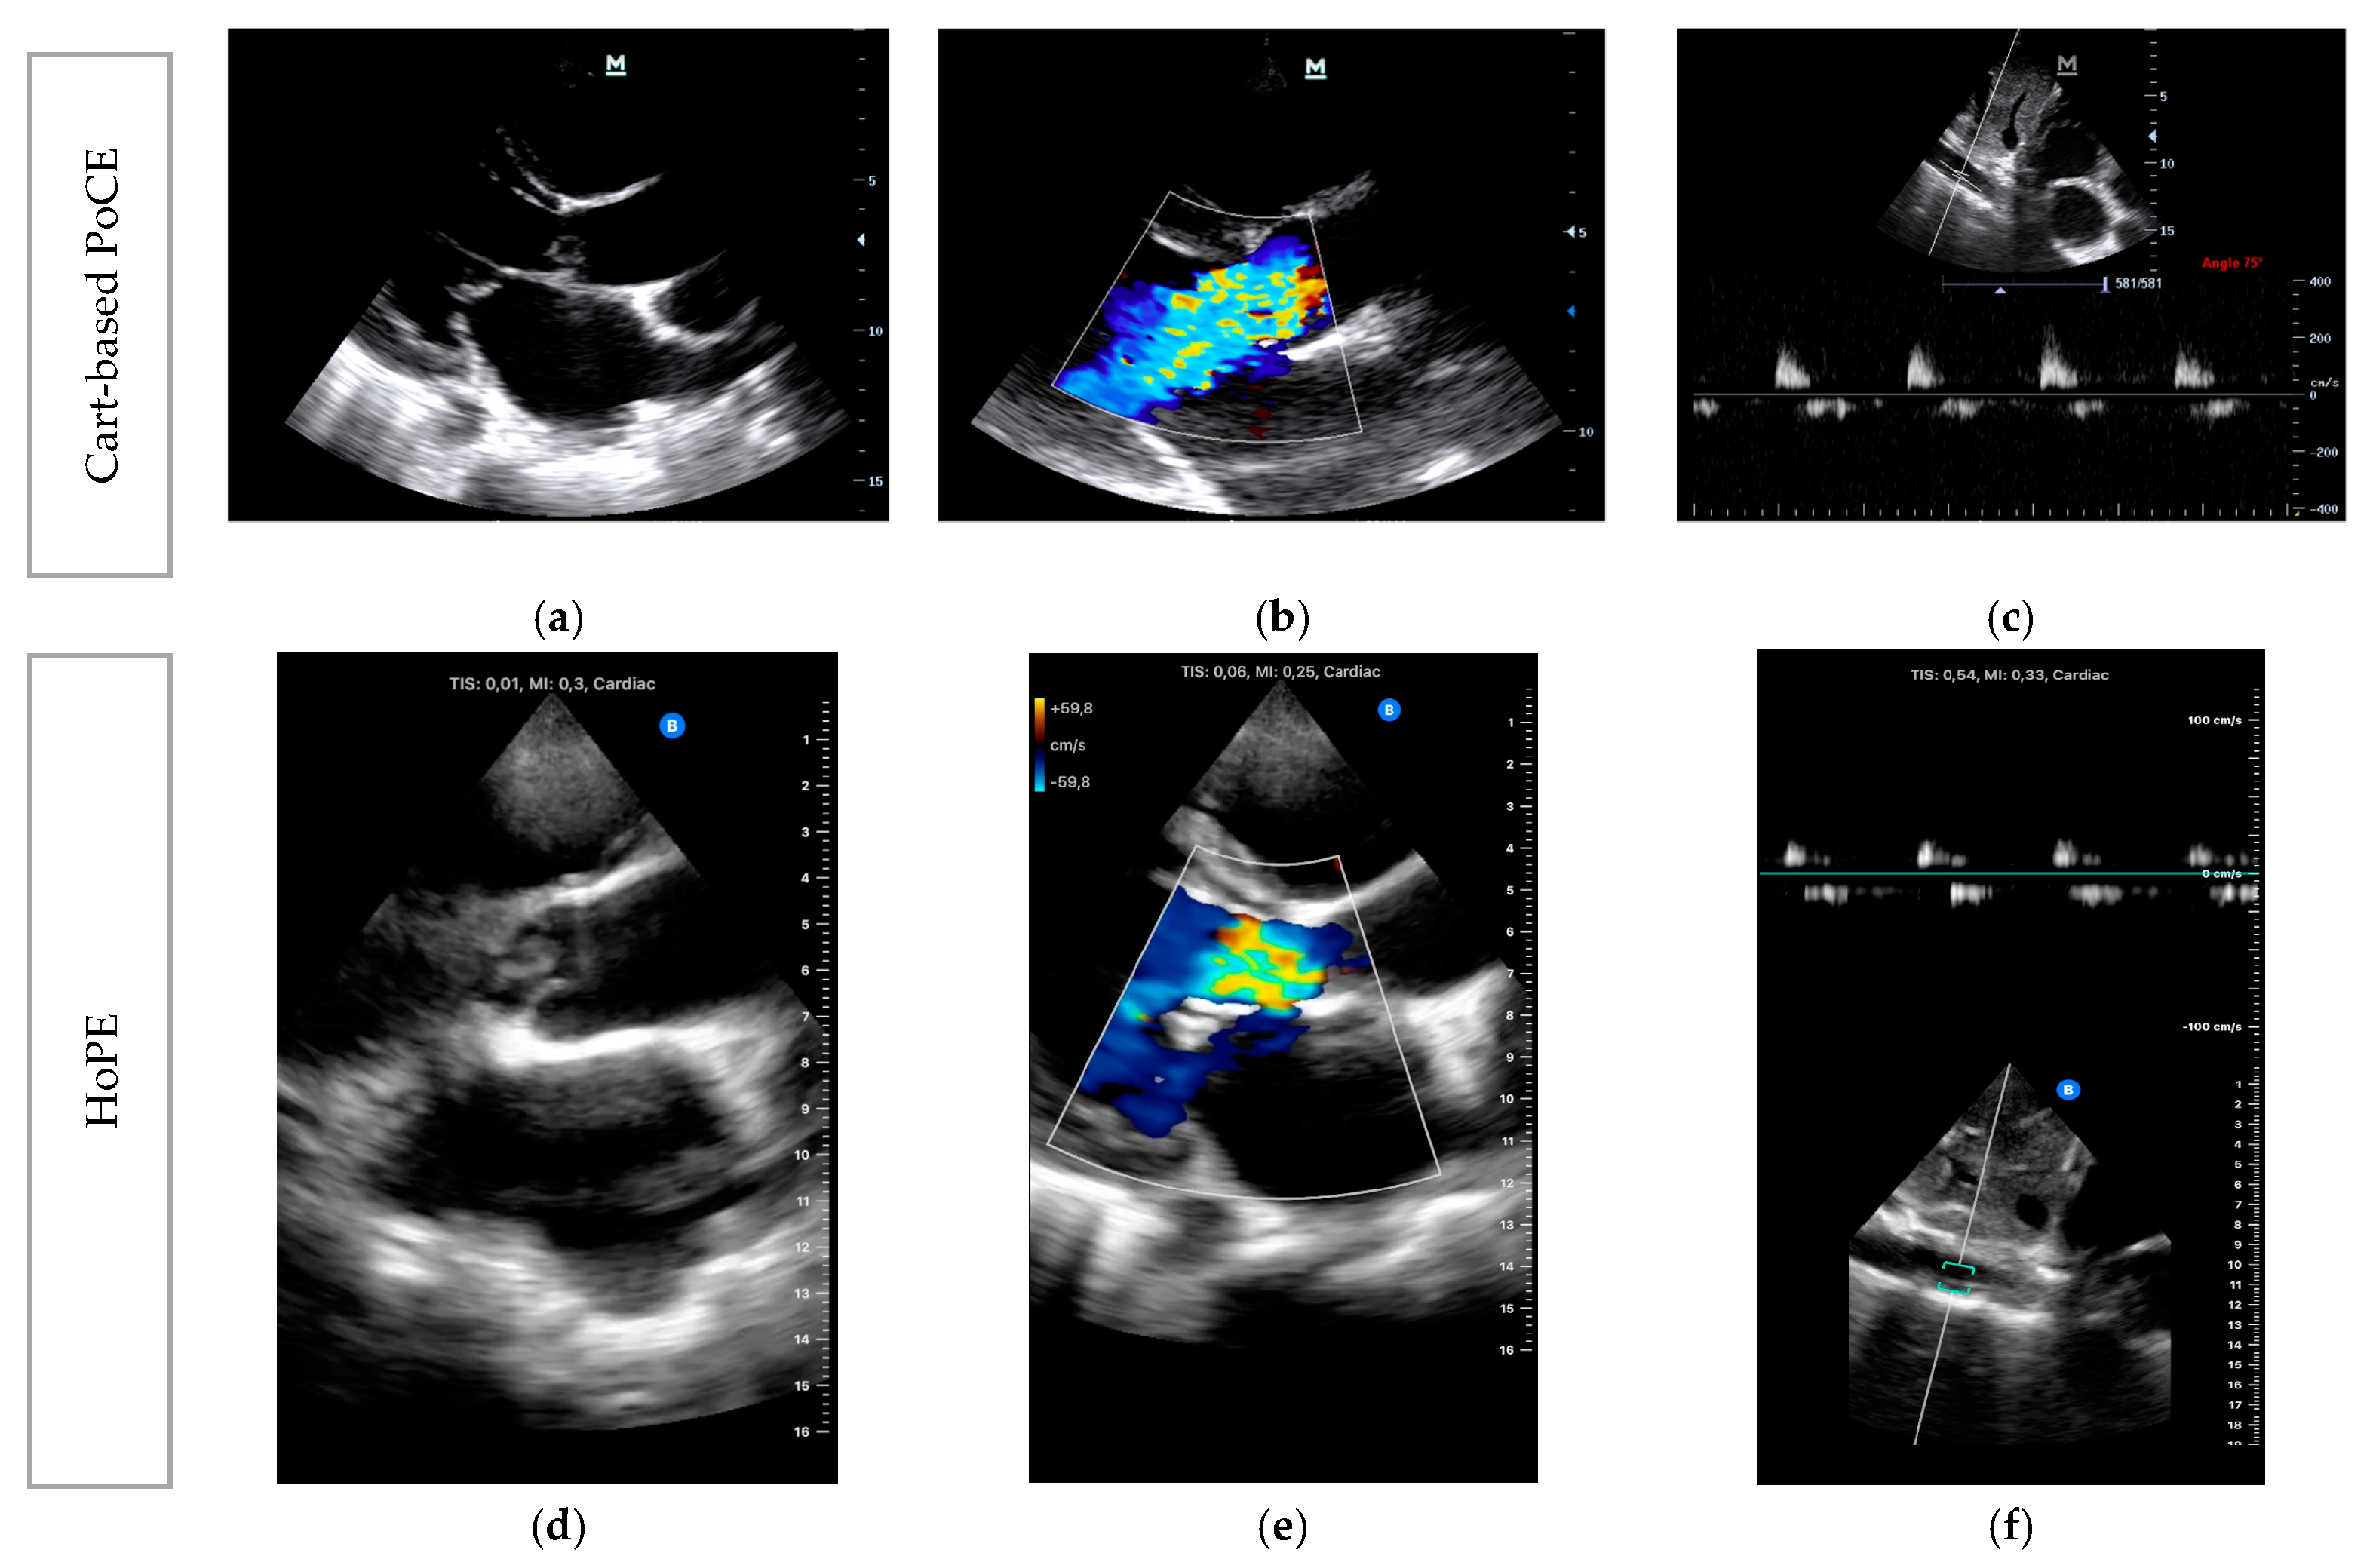

- Imaging ModesVarious ultrasound modalities are used to assess the structure and function of heart valves. Two-dimensional (2D) imaging is generally used for structural assessment, colour flow doppler (CFD) is used to evaluate blood flow across the valves, and continuous-wave (CWD) and pulsed-wave doppler (PWD) techniques are used to measure flow velocities and gradients across valves. Integrating these imaging modalities can offer a comprehensive assessment of valvular function and aid in identifying specific pathologies (Table 1) [27,38].

| Colour Flow Doppler (CFD) | Colour flow is not a good marker for assessment of severity of MR or AR. However, it may assist with determining aetiology—usually eccentric jets if prolapse/flail in the direction that is away from the prolapsing/flail leaflet i.e., anterior mitral valve leaflet prolapse leads to a posteriorly directed jet. | Central jet, typically directed towards the posterior wall of the left ventricle. |

| Continuous Wave Doppler (CWD) | Increase in forward flow velocity with “V-wave” cut off. Equal colour density between forward flow and regurgitant doppler traces. Systolic flow reversal in 3 out of 4 pulmonary veins. | Increase in forward flow velocity. Pressure half time <200 ms. Doppler trace of AR ends before the end of diastolic due to early equilisation of aortic and LV pressures. Equal colour density between forward flow and regurgitant doppler traces. |

| Pulse Wave Doppler (PWD) | Systolic reversal of flow in pulmonary veins. | Diastolic flow reversal in the descending thoracic aorta. |